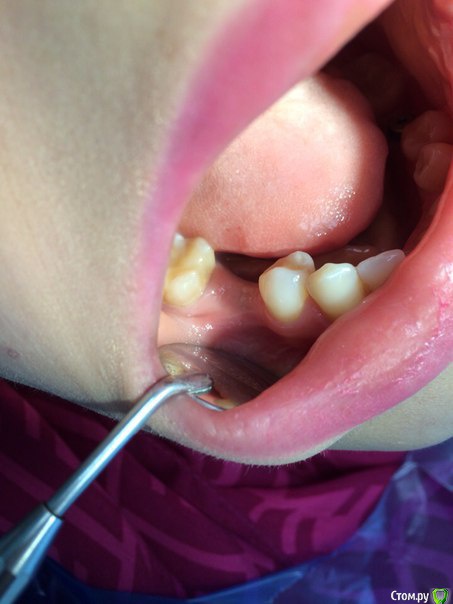

Кариес+ Опубликовано 18 октября, 2015 Поделиться Опубликовано 18 октября, 2015 Зравствуйте коллеги имею не большой опыт в имплантации есть некоторые вопросы. планируется операция в области 4.6 , судя по кт есть небольшое просветление у вершины гребня , будет ли там кость или готовиться к нкр? Ссылка на комментарий

Кариес+ Опубликовано 18 октября, 2015 Автор Поделиться Опубликовано 18 октября, 2015 на фото полости рта это другой клинический случай. там уже стоит импланта и планируется установка формирователя Ссылка на комментарий